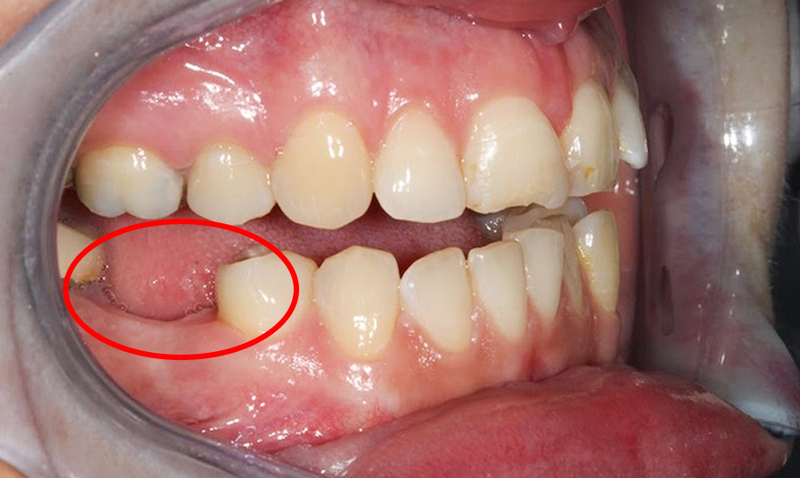

2.5 Mất răng số 7 có niềng răng được không?

Răng số 7 là răng hàm trong cùng. Khi mất răng này, ảnh hưởng đến khớp cắn thường không quá nghiêm trọng nếu răng số 6 còn khỏe. Nhiều trường hợp vẫn có thể niềng bình thường mà không cần trồng lại răng số 7, trừ khi mất răng hai bên gây lệch khớp cắn.